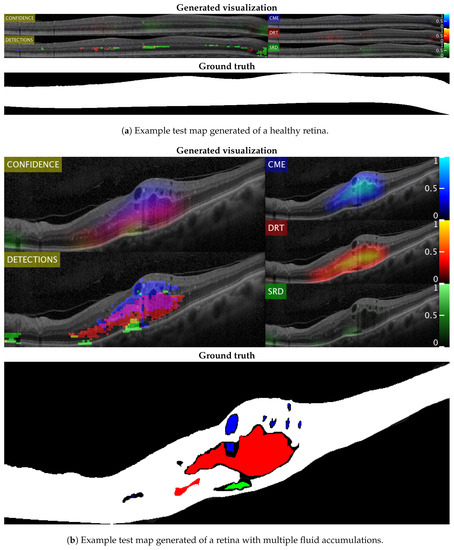

Figure 14 and Figure 15 show representative examples from the test set with a healthy image and another one with different types of pathological fluid generated with the Spectralis and Cirrus devices, respectively. In addition, the labels of the expert are included to compare with the results. As can be seen, in both cases, the system is capable of satisfactorily detecting the pathological fluid accumulations whenever they are present, although we can see spurious detections in the cases of both Figure 14a and Figure 15a. However, these detections can be easily corrected with post-processing strategies as mentioned before, but we decided to include them for a better understanding of the behavior of the system.

Figure 14.

Test visualizations generated using images from the Spectralis device.

In these visualizations, we can observe two major phenomena. The first one consists in the tendency to spurious detections in the images generated by the Spectralis of the SRD-type edema. This may be due to the higher contrast of the images generated by this device, favouring the appearance of common patterns of the SRD-type edema not present in the images that are generated with Cirrus. On the other hand, we can see a clear tendency in the Cirrus images to generate small detections of DRT-type edema. This is due to what was already mentioned in the section where we analyzed the selection of features: the DRT pattern of the images that are generated with the Cirrus device is very similar to the normal tissue in comparison with the "wet" and coarse texture of the DRT fluid accumulations in images that are generated with the Spectralis device.

In the images that were used for testing, we have found an example of each of these extreme cases, represented in Figure 16. In this figure, we see the particular case of an Spectralis image with dark regions detected as SRD (Figure 16a) and a particular case of a Cirrus image with slightly thickened layers that was detected as DRT (Figure 16b).